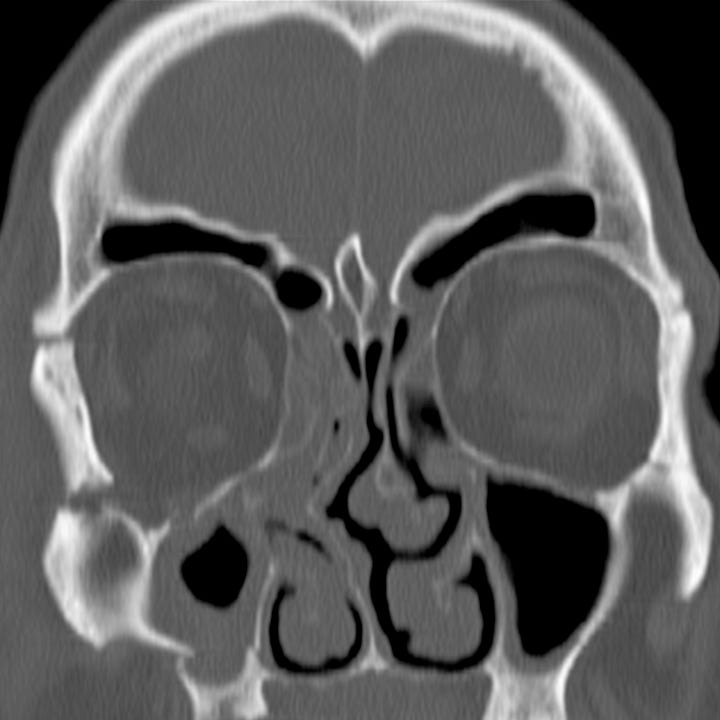

Fig. (2). Coronal CTscan image showing a severely dislocated zygomatic Radiology Zygomaticomaxillary Complex Fracture zygomaticomaxillary complex fracture is characterised by fractures involving: zygomatic complex fracture is second most common mid face fracture and frequent amongst the maxillofacial. the detection of fractures of the facial zygomatic complex, with orbital compromise, is essential for surgical. zygomaticomaxillary complex fracture is one of the most commonly. the zygomaticomaxillary complex (zmc) has important aesthetic,. Radiology Zygomaticomaxillary Complex Fracture.

From opendentistryjournal.com